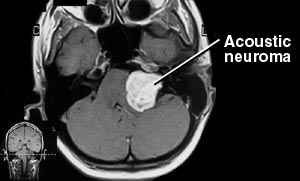

Acoustic Neuroma

Acoustic neuromas, also known as acoustic schwannomas, acoustic neurinomas, vestibular schwannomas, and vestibular neurilemomas, are Schwann cell derived tumors commonly arising from the vestibular portion of the eighth cranial nerve. They account for approximately 8 percent of intracranial tumors in adults and 80 to 90 percent of cerebellopontine angle tumors (CPAs). In comparison, they are rare in children without neurofibromatosis.